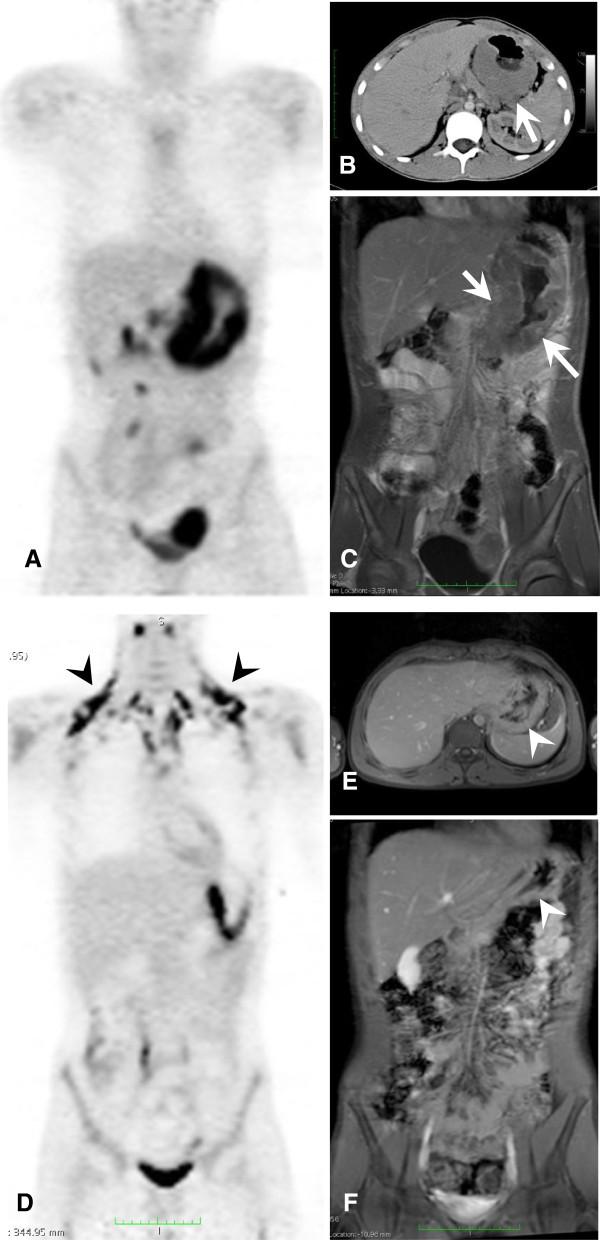

This study is to evaluate the predictive value of FDG-PET (PET) in pediatric and adolescent patients suffering from non-Hodgkin lymphoma (pNHL) in comparison to information provided by conventional imaging methods (CIM).

Imaging was performed at baseline and at interim (after 2 cycles of chemotherapy). The response assessment in PET was carried out visually and semi-quantitatively, the latter one by use of percentage decrease in SUVmax from baseline to interim (ΔSUVmax). The PET-based results were compared to the findings by CIM. Progression-free survival (PFS) was analyzed using Kaplan-Meier curves (KM) and log-rank test.

The final study included 16 patients (mean follow-up time, 60.2 months (range, 4.0 to 85.7 months)). Relapse occurred in four patients. Visual PET compared to CIM revealed higher sensitivity (3/4 vs 1/4) and NPV (6/7 vs 10/13), and equal PPV (3/9 vs 1/3), but lower specificity (6/12 vs 10/12) and accuracy (9/16 vs 11/16). False-positive findings in PET at interim were predominantly observed in patients presenting bulky disease (5/6), whereas CIM was true-negative in all of these cases. KM analyses revealed no significant differences in 5-year PFS neither for CIM (76.9% vs 66.7%; p = 0.67) nor for visual PET (85.7% vs 66.7%; p = 0.34) nor for ΔSUVmax (88.9% vs 57.1%; p = 0.12).

The predictive value of iPET in pediatric patients suffering from NHL was limited due to considerably high amount of false-positive findings, especially in patients suffering from bulky disease. However, due to our limited sample size, final conclusions cannot be drawn and, thus, call for further evaluation of PET in pNHL in larger and more homogenous patient series.

本研究旨在评估 FDG-PET(PET)在儿科和青少年非霍奇金淋巴瘤(pNHL)患者中的预测价值,并与常规影像学方法(CIM)提供的信息进行比较。

在基线和中期(化疗 2 个周期后)进行影像学检查。通过视觉和半定量方法进行 PET 反应评估,后者使用 SUVmax 从基线到中期的百分比下降(ΔSUVmax)进行。将基于 PET 的结果与 CIM 的结果进行比较。使用 Kaplan-Meier 曲线(KM)和对数秩检验分析无进展生存期(PFS)。

最终研究纳入 16 例患者(中位随访时间为 60.2 个月(范围为 4.0 至 85.7 个月))。4 例患者复发。与 CIM 相比,视觉 PET 显示出更高的敏感性(3/4 对 1/4)和阴性预测值(6/7 对 10/13),相同的阳性预测值(3/9 对 1/3),但较低的特异性(6/12 对 10/12)和准确性(9/16 对 11/16)。中期 PET 的假阳性发现主要见于存在巨大肿块的患者(5/6),而 CIM 在所有这些情况下均为真阴性。KM 分析显示,无论是 CIM(76.9%对 66.7%;p=0.67)还是视觉 PET(85.7%对 66.7%;p=0.34)或ΔSUVmax(88.9%对 57.1%;p=0.12),5 年 PFS 均无显著差异。

由于存在大量假阳性发现,特别是在患有巨大肿块的患者中,iPET 在儿科 NHL 患者中的预测价值受到限制。然而,由于我们的样本量有限,无法得出最终结论,因此需要在更大、更同质的患者系列中进一步评估 PET 在 pNHL 中的应用。